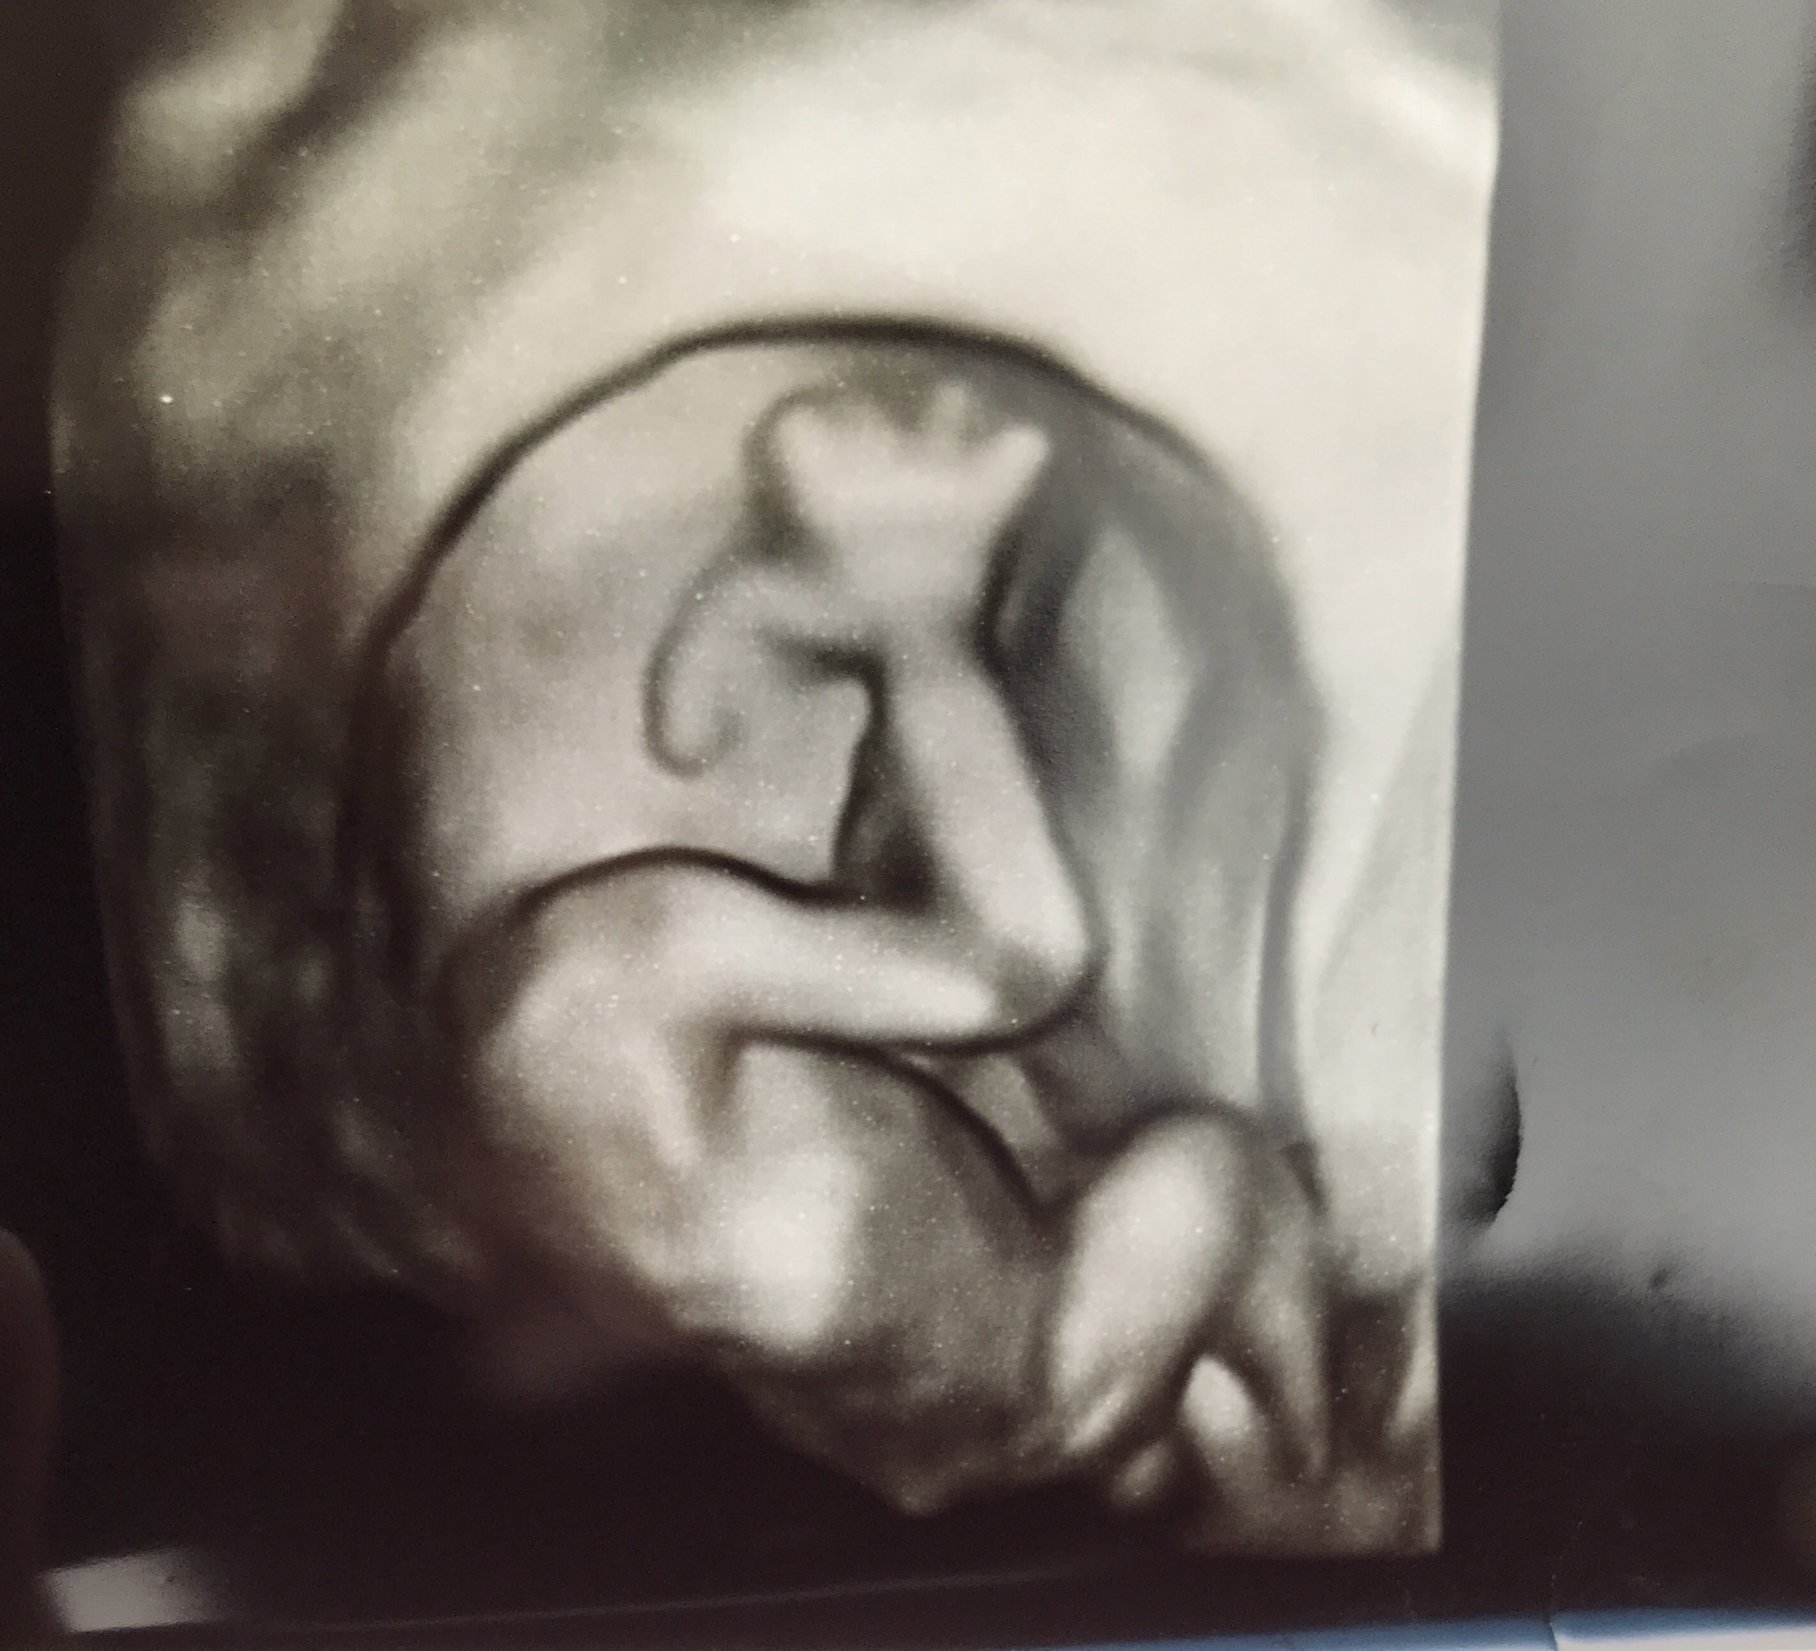

I'm 12w5d but measuring at 13w4d (!!!) I got to see my little bean bouncing around all over the place, and moving it's arms all over.

ETA picture since it didnt post the first time